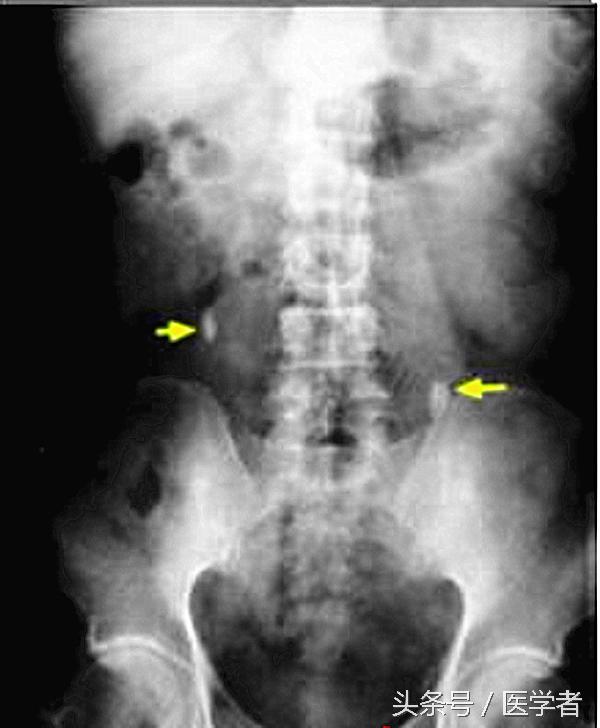

(2)尿路平片:即腹部平片,能发现90%以上的X线阳性结石。

诊断尿路结石首选的检查为腹部平片+静脉尿路造影。